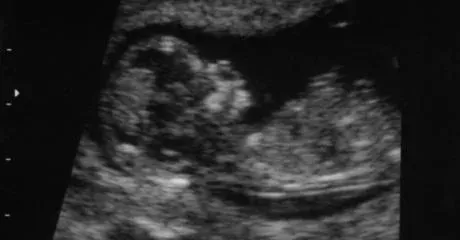

At the origin of this strange anomaly there is a dysfunction that occurs during the development of the embryo. During a classic pregnancy with twins, two different oocytes can be fertilized by two different sperm. They then give birth to what is known as “non-identical twins” or more scientifically “fraternal twins”.

But during the first stages of development, it is possible that one of the two embryos literally “absorbs” its twin, and thus becoming one. “The two zygotes merge and form only one human with two different cell linings,” explains doctor Brocha Tarshish, geneticist at Nicklaus Children’s Hospital in Miami, United States. It is this phenomenon which seems to affect Taylor Muhl.